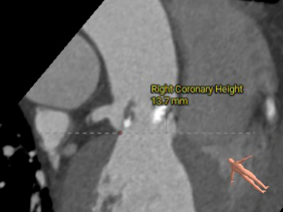

右冠开口高度:13.7mm

左窦瓣叶长度:15.2mm

右窦瓣叶长度:16.6mm